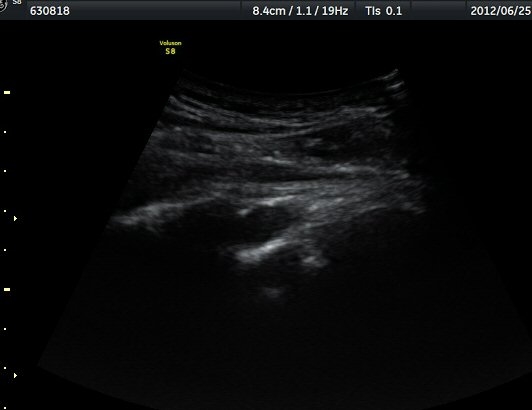

¿ª½Ã °ß°©°ñ °¡½Ãµ¹±â(spine) ¾Æ·¡¿¡¼­ Àú¿¡ÄÚ ³¶Á¾ÀÌ °üÂûµÈ´Ù(±×¸² 2). º¼·ÏŽÃËÀÚ·Î ¹Ù²Ù¾î °ü

ÂûÇÏ´Ï  °¡½Ãµ¹±â°üÀý¼ø°í¶û¿¡¼­ Àú¿¡ÄÚ ³¶Á¾ÀÌ ´õ¿í ¶Ñ·ÈÈ÷ °üÂûµÈ´Ù(±×¸² 3, 4).

ÁÖ»ç¹Ù´Ã ÈíÀÎ(µ¿¿µ»ó Âü°í) 4ÀÏ ÈÄ °üÂûÇÑ ¼Ò°ß¿¡¼­´Â ³¶Á¾ÀÇ Å©±â °¨¼Ò°¡ ¶Ñ·ÈÇÏÁö ¾Ê´Ù(±×¸² 5, 6).